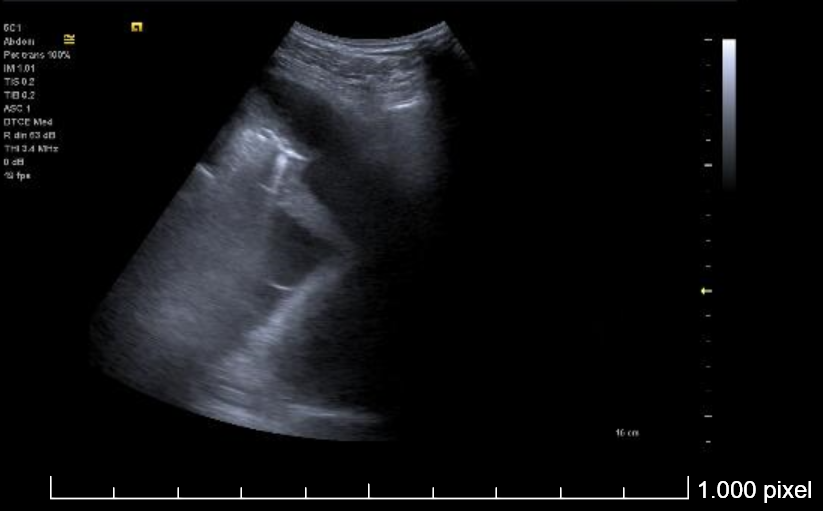

Derrame pleural izquierdo de 4 espacios intercostales, libre, hipoecogénico, sin ecos internos. Lóbulo pulmonar inferior izquierdo con imagen de patrón mixto (Intersticial y consolidación).

Se realiza toracocentesis diagnóstica y evacuadora con la paciente en decúbito lateral derecho. Se drenan un total de 550 cc en total de LP serohemático (pH en gasómetro 7.58).